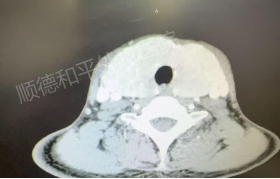

历经11.5小时的切除成果